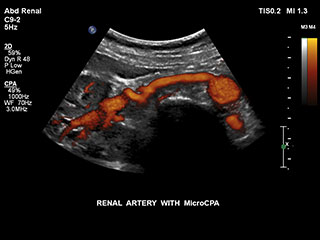

Получение информации о кровотоке в мелких сосудистых структурах с небольшим кровотоком традиционно считается сложной задачей. Благодаря новой функции MicroCPA в системе EPIQ визуализация капиллярного кровообращения с низкой скоростью кровотока выполняется быстро и просто, обеспечивая более точную диагностику при оценке перфузии органов и сети небольших сосудов.